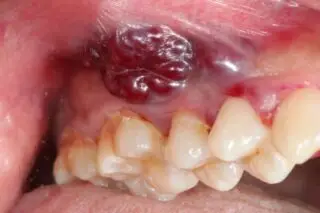

Oral cancer is usually found when a person notices some changes taking place in their mouth. Some of the common symptoms of oral cancer can be:

- A sore in your mouth or on your lip that is not healing

- A lump in your throat, in your mouth, or on your lip

- A red or white patch in the lining of your mouth, your tongue, or on the gums

- Abnormal numbness, pain, or bleeding in your mouth